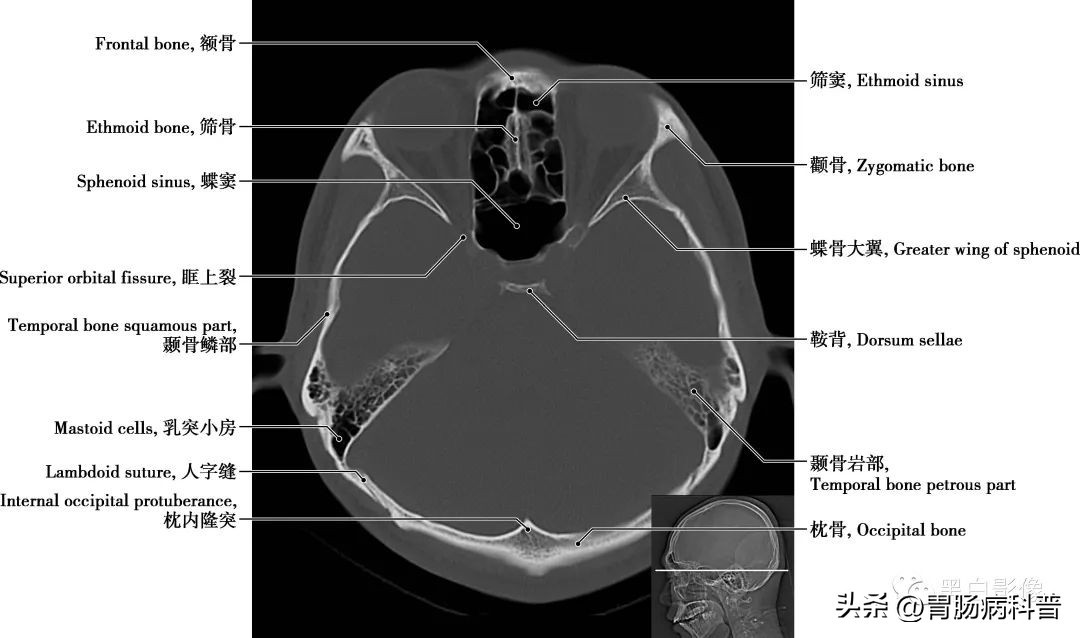

图1-2-13 经海绵窦轴位切面

蝶骨大翼 由蝶骨体部平伸向两侧,继而上翘,可分三个面,脑面位于颅中窝,眶面朝向眶,颞面向外向下。在蝶骨大翼近根部处由前向后可见圆孔,卵圆孔和棘孔,从棘孔入颅的脑膜中动脉在骨面上留有动脉沟。其后缘是颅后窝和颅中窝的分界线

图1-2-14 经第四脑室中央轴位切面

颞骨岩部 岩部前上面位于颅中窝,中部有一弓状隆起,外侧为鼓室盖,靠近锥体尖处,有稍凹的三叉神经压迹;其后上面位于颅后窝,近中央处有内耳门。后上面和前上面相接处为岩部上缘。岩部下面近中央部有颈动脉管外口,颈动脉管在岩部内侧半通过,在锥体尖处形成颈动脉管内口;外口的后方为颈静脉窝,它与后方枕骨上的颈静脉切迹围成颈静脉孔